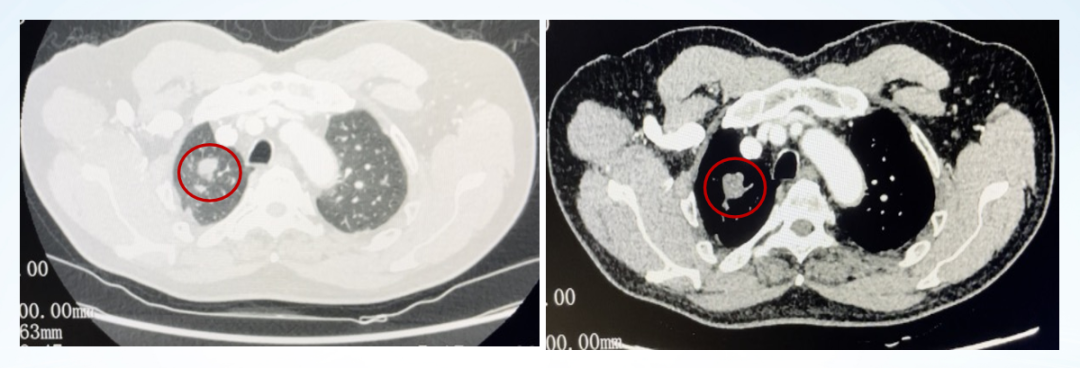

影像学评估:

图22、呋喹替尼治疗期间,患者肺部转移灶胸部增强CT评估情况:左(2020-10-23)、中(2021-05-27)、右(2021-07-06)

图23、呋喹替尼治疗期间,患者口腔颊黏膜转移灶口腔增强CT评估情况:左(2020-10-23)、中(2021-05-27)、右(2021-07-08)

疾病进展:2021年8月,患者出现咳胸闷,咳嗽。胸部CT提示双肺转移瘤相仿,右侧支气管内多发软组织密度影。

图24、胸部增强CT显示支气管内新增转移病灶:左(2021-07-06)、右(2021-08-31)